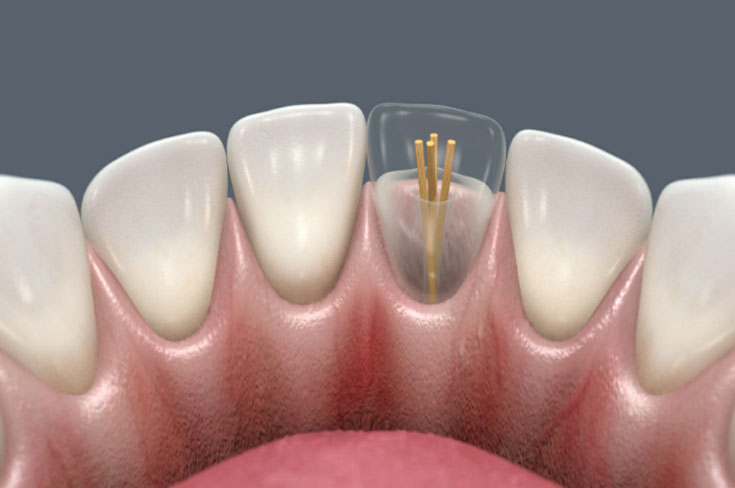

-

Установка штифтов: В каналы вводится специальная паста, после чего устанавливаются штифты - сначала основные, затем меньшие по диаметру. Это обеспечивает надежную фиксацию и поддержку для будущей реставрации.